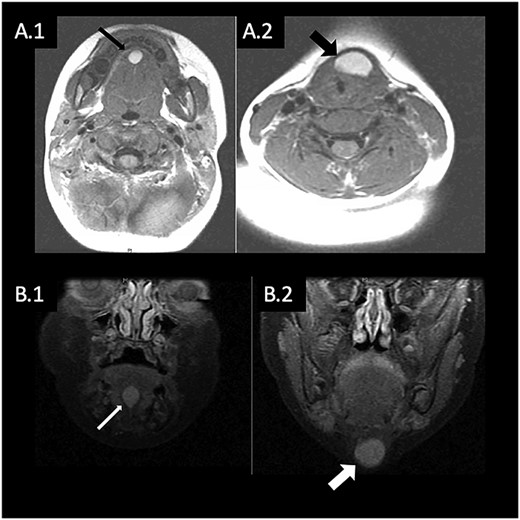

(A) T1 weighted MRI in axial plane showing hyperintense mass in the FOM (A.1) and anterior neck (A.2); (B) T1 weighted MRI in coronal plane showing hyperintense mass in the FOM (B.1) and anterior neck (B.2).

A 9-month-old girl presented with a 5-month history of an asymptomatic midline neck mass located at the level of the thyroid gland. The magnetic resonance imaging (MRI) demonstrated a lesion in the anterior neck slightly left of midline, with a second cystic structure incidentally found within the FOM (Fig. 1). The initial differential for these masses included dermoid cyst, epidermoid or rare intestinal foregut cyst. Interestingly, the anterior neck mass showed evidence of a connection to the FOM mass, but no connection to the foramen cecum. As such, TGDC was lower on the differential. An ultrasound again revealed a midline cystic mass extending to the FOM with features suggestive of a dermoid cyst. On repeat physical exam, a small cystic mass in the FOM was palpated, without any obstruction of the oral cavity or airway. Surgical excision of both lesions was recommended. The patient was initially lost to follow up and returned for reassessment at 4 years of age. At that time, there was incremental change in the size of the lesions.

Radiographic imaging plays an important role in evaluating a neck mass. Imaging can reveal the extent of involvement and aid surgical planning. Ultrasound can be used for typical cases of TGDC and is also useful in confirming the presence of a normal thyroid gland in the case of ectopic thyroid tissue. In the cases of atypical TGDC reviewed here, MRI or computed tomography imaging were obtained to evaluate the masses further. In our case, the FOM mass was only identified after MRI.